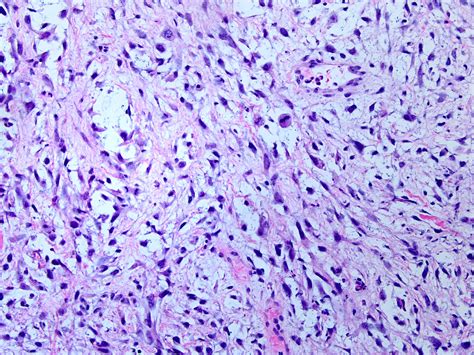

Receiving a medical diagnosis involving the term Spindle Cell Neoplasm can be an overwhelming experience, often filled with uncertainty and concern. To navigate this diagnosis effectively, it is essential to understand what these cells are, how they behave, and why this term is used as a broad descriptor rather than a final, specific diagnosis. At its core, this term refers to a group of tumors characterized by the presence of elongated, spindle-shaped cells when viewed under a microscope. Because many different types of tissue can produce these specific cell shapes, the diagnosis is essentially a starting point for pathologists to determine the exact nature and origin of the growth.

In pathology, the term Spindle Cell Neoplasm is a descriptive classification. It tells a medical team that a biopsy has revealed cells that are longer than they are wide—resembling the shape of a sewing spindle—but it does not immediately clarify whether the tumor is benign (non-cancerous) or malignant (cancerous).

These cells are structural components of the body’s connective tissues, including muscle, fat, fibrous tissue, and nerves. When these cells begin to grow uncontrollably, they form a mass that pathologists identify as having "spindle cell morphology." Because this morphological trait is shared by a vast array of conditions, pathologists must perform secondary testing, such as immunohistochemistry, to identify specific proteins or markers present on the cells.